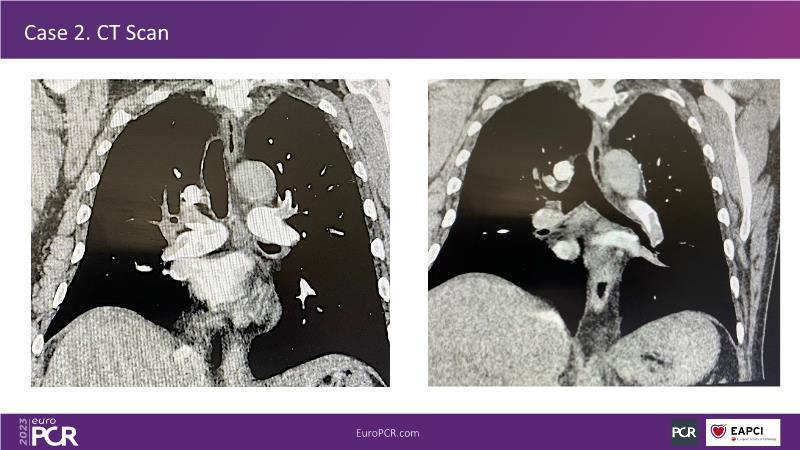

Primary percutaneous pulmonary intervention (pPPI) of acute pulmonary embolism with computer-aided mechanical aspiration

Summary

As there is a need for more awareness, training and data on primary percutaneous pulmonary intervention, watch this session to learn from shared pioneering experience!